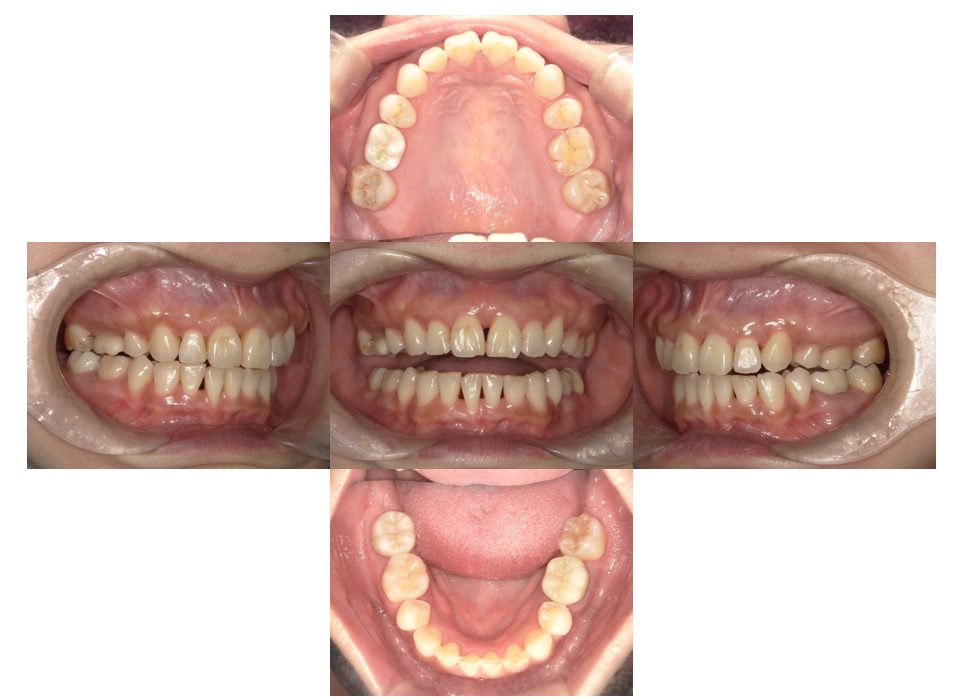

矯正治療・セラミック治療の症例紹介(三隅歯科クリニック)

三隅 賢祐(三隅歯科クリニック)

症例詳細

| 主訴 | 30代女性 口腔内にコンプレックスがあるから綺麗にしたい |

| 治療内容 | 矯正治療を行いました。 |

| 治療費 | 1,700,000円(税込み) |

| 治療期間 | 4年(矯正治療期間 3年) |

| 治療回数 | 50回 |

| 想定されたリスク | 前歯部の欠損が絡んだケースだったので、歯槽骨の吸収の具合によって骨造成か歯肉移植の必要性が出る可能性があった。 |